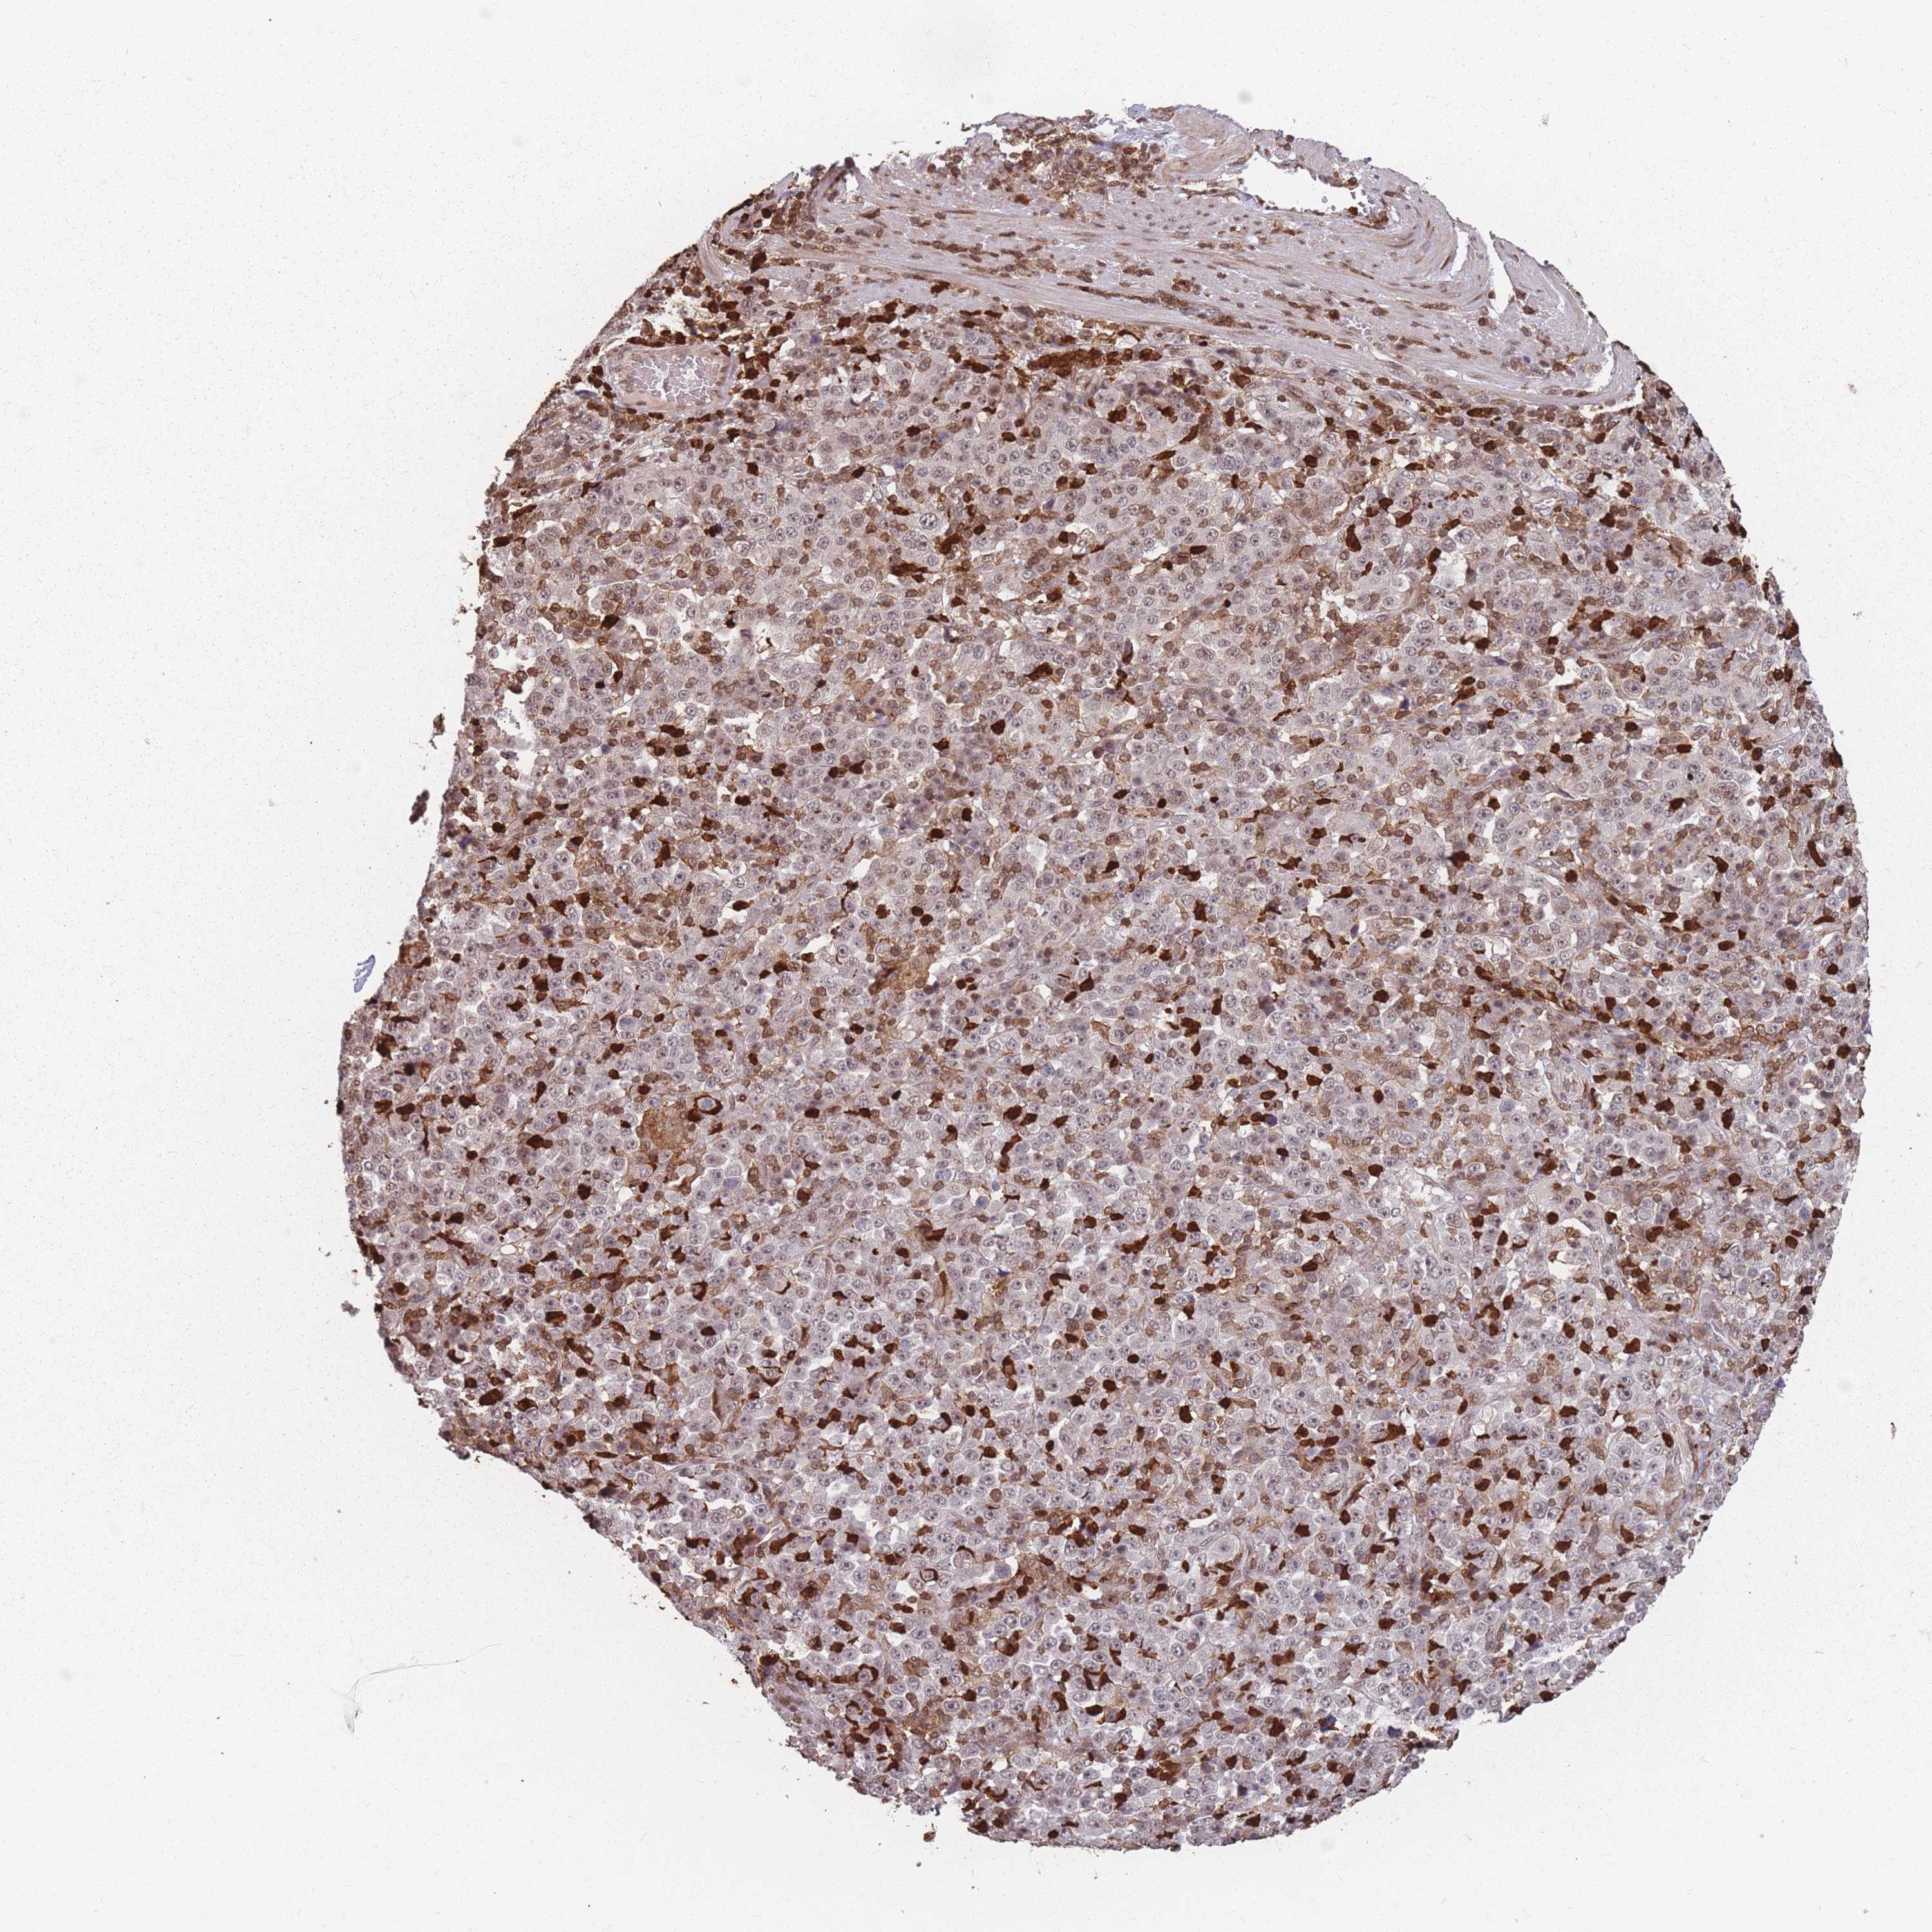

STOMACH CANCER - Protein expressioni

A mouse-over function shows sample information and annotation data. Click on an image to view it in a full screen mode. Samples can be filtered based on level of antibody staining by selecting one or several of the following categories: high, medium, low and not detected. The assay and annotation is described here.

Note that samples used for immunohistochemistry by the Human Protein Atlas do not correspond to samples in the TCGA dataset.

Antibody stainingi

Antibody staining in the annotated cell types in the current human tissue is reported as not detected, low, medium, or high, based on conventional immunohistochemistry profiling in selected tissues. This score is based on the combination of the staining intensity and fraction of stained cells.

Each image is clickable and will lead to virtual microscopy that enables deeper exploration of all samples and also displays staining intensity scores, fraction scores and subcellular localization as well as patient and tissue information for each sample.

Antibody HPA043470

Antibody HPA048143

Staining

High

Medium

Low

Not detected

Intensity

Strong

Moderate

Weak

Negative

Quantity

>75%

75%-25%

<25%

None

Location

Nuclear

Cytoplasmic/membranous

Cytoplasmic/membranous,nuclear

Adenocarcinoma, NOS